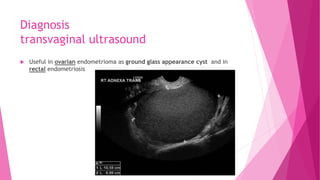

transvaginal ultrasound

 Useful in ovarian endometrioma as ground glass appearance cyst and in

rectal endometriosis